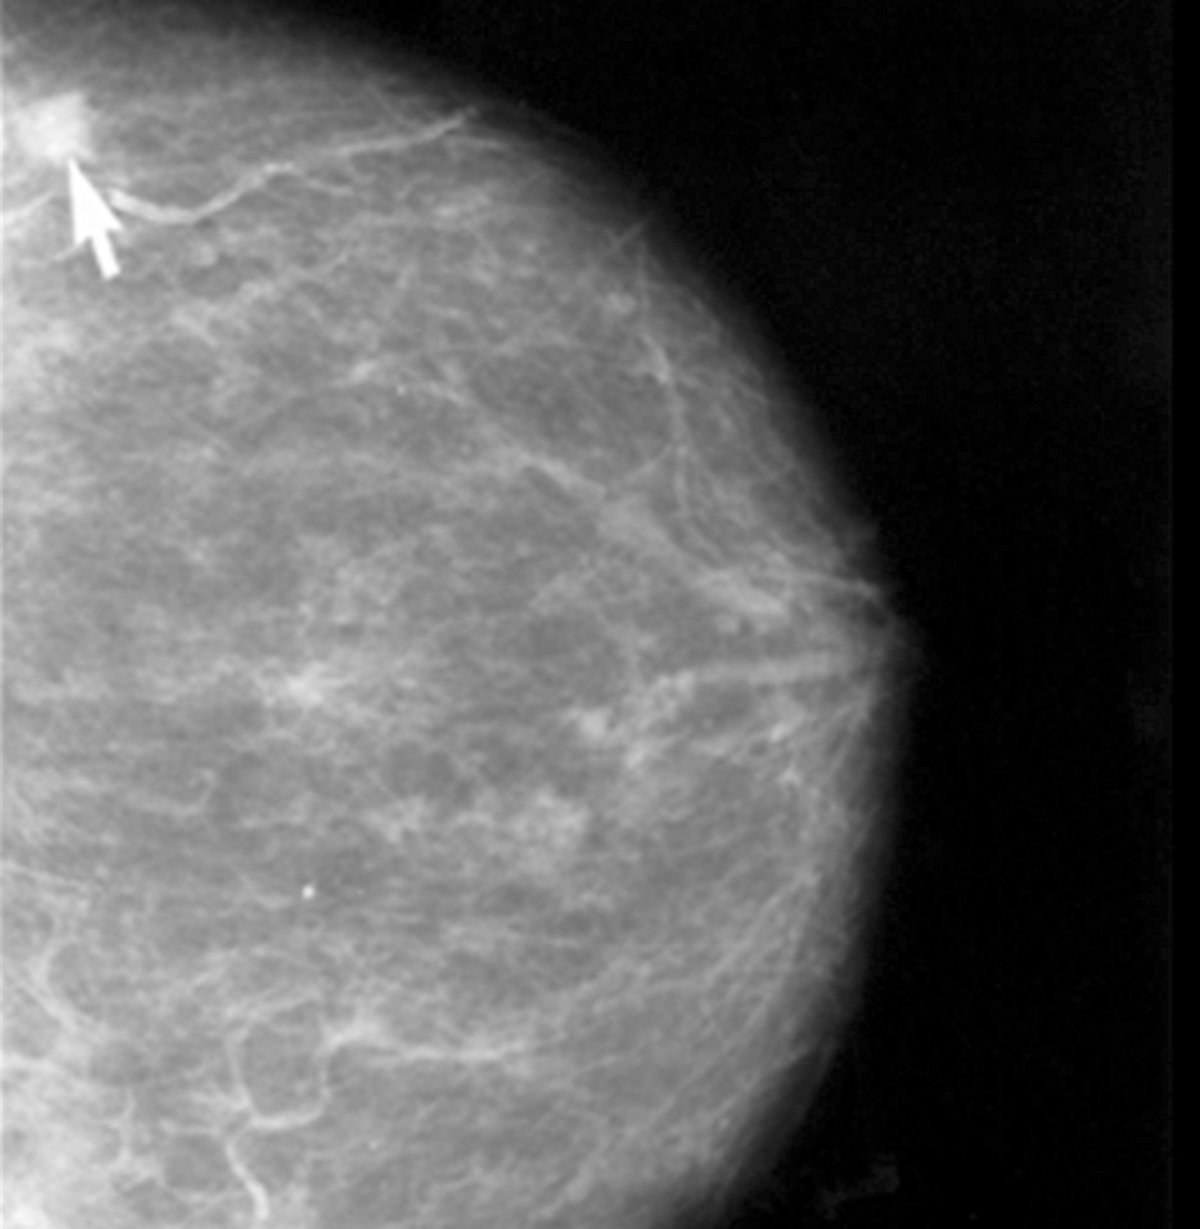

Los hábitos saludables evitarían el 26% de cánceres de mama

Cáncer de Mama

Un estilo de vida saludable basado en comer frutas y verduras, no fumar, no beber alcohol y realizar actividad física reduce el riesgo de sufrir varios tipos de cáncer, como el de colon en un 37% y el de mama en un 26%, según se recoge en el libro 'Nutrición y cáncer, lo que la ciencia nos enseña', elaborado por el doctor Carlos Alberto González, de la Unidad de Nutrición del Instituto Catalán de Oncología (ICO).

Los estudios indican que no fumar, seguir una dieta rica en frutas y verduras, mantener un peso normal, realizar actividad física de forma regular y no beber alcohol o hacerlo con moderación reduce el riesgo de cáncer de colon en un 37%, el de cáncer de mama en un 26% y el cáncer gástrico en un 51%.